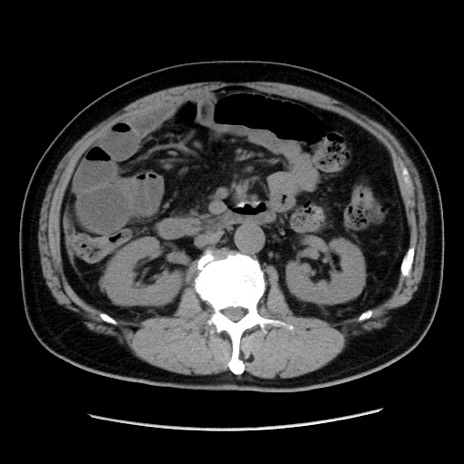

症例16(横断像)

冠状断像

【症例】 70歳代男性

【主訴】 腹痛、嘔吐

【現病歴】 約1ヶ月前より間欠的に腹痛と嘔吐あり、当院消化器内科を受診したところCTで多発する肝臓のLDAを指摘され、精査中であった。以降は消化器症状は安定していたが、2日前より嘔気と腹痛があり、同日より排便・排ガスが消失した。改善認めず、 本日、救急外来を受診した。

【既往歴】 大腸ポリープ切除後。

【身体所見】意識清明・会話良好、BT 36.3℃、BP 127/80mmHg、 P 80bpm、腹部:膨満あり、平坦・軟、上腹部正中および下腹部正中に圧痛あり、反跳痛なし、筋性防御なし。

【データ】WBC 7200、CRP 0.77